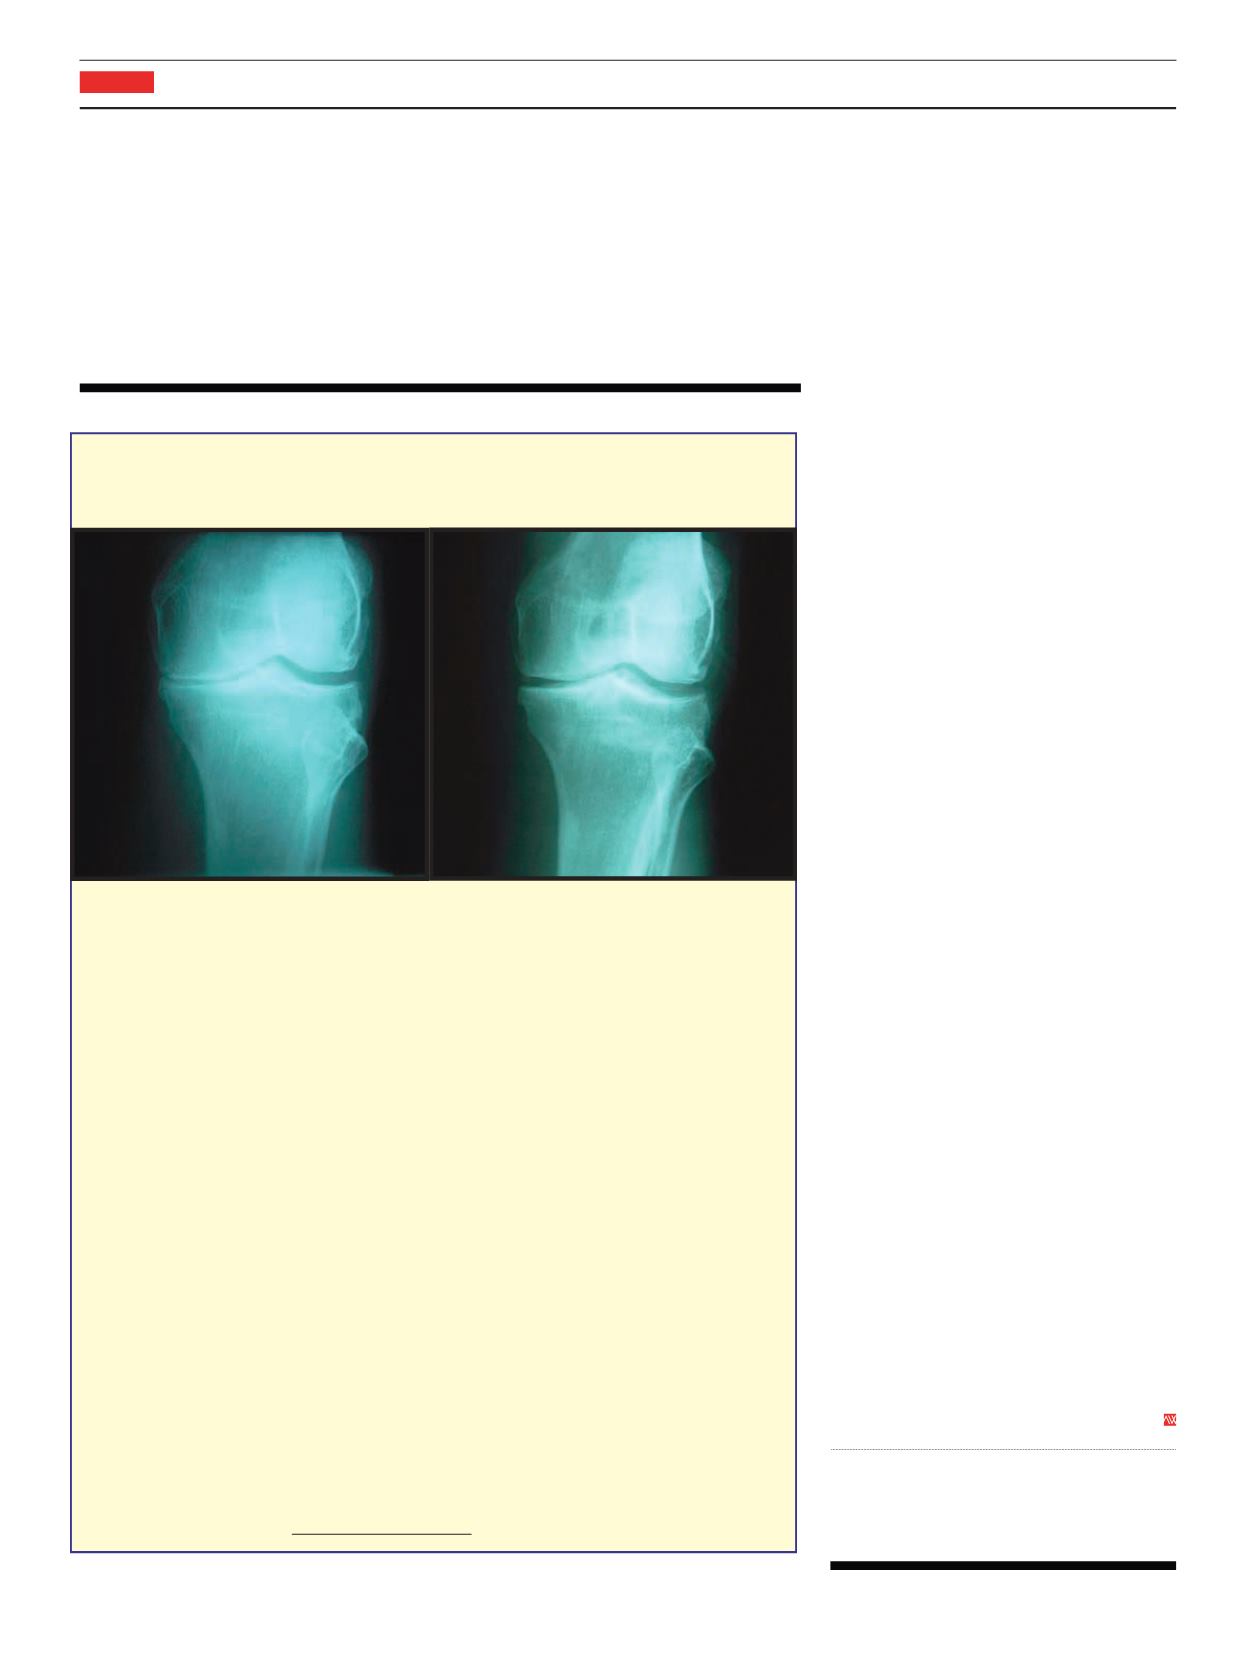

SJ is a 60-year-oldmalewith the chief complaint of knee painwho visited

TheCenter for RegenerativeMedicine over a year ago.Hewas diagnosedwith bone-on-bone

osteoarthritis of the left knee, causingmuchpain anddiscomfort; at that point hewas told

only a total knee replacement couldhelphim.He is otherwise healthy.On examhe had

point tenderness to themedial side of the left knee (medical lingo: inner side). AnX-ray

showed severe arthritis of the knee (X-ray on the left). Patient started receiving treatments

atTheCenter for RegenerativeMedicine.Today he is feeling better (X-ray on the right).